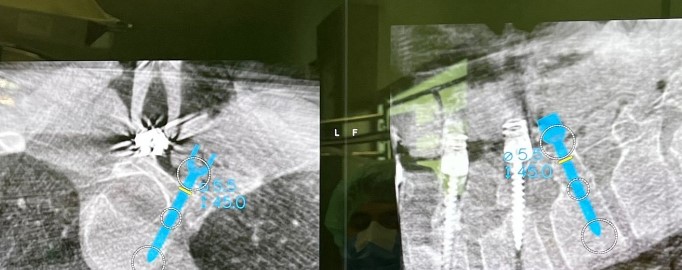

“La chirurgia computer assistita effettua una scansione navigata tridimensionale della colonna vertebrale che, integrando le immagini con tac e risonanza magnetica eseguite preventivamente, ricostruisce su due monitor una sorta di modellino: questo permette al chirurgo di pianificare pre-operatoriamente il posizionamento delle viti calcolando le coordinate da seguire intraoperatoriamente, grazie ad un sistema di tracciamento in tempo reale e ad un algoritmo di intelligenza artificiale, per il loro esatto posizionamento”, spiega il dottor Andrea Piazzolla, responsabile della Unità Operativa di Chirurgia Vertebrale.